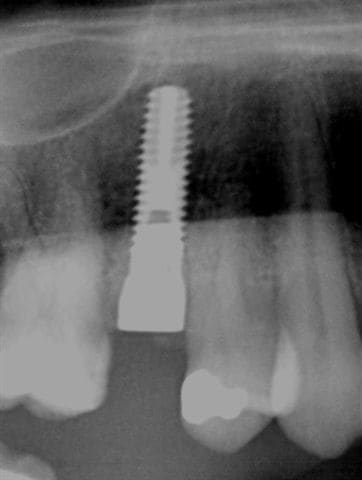

mais dans la mesure du possible implantes tout de suite. Ci joint radio d'une prémolaire que je vais extraire demain matin avec implantation immédiate.

suite de la prémolaire fracturée: extraction , mise en place d'un implant tekka diametre 4 longueur 15 mm pour aller chercher un bon ancrage primaire. Il y avait 2 mm d'espaceentre l'implant et la corticale en vestibulaire et 1 mm en palatin, j'ai comblé au bio-oss et tracté la muqueuse sans tensions pour le recouvrir.